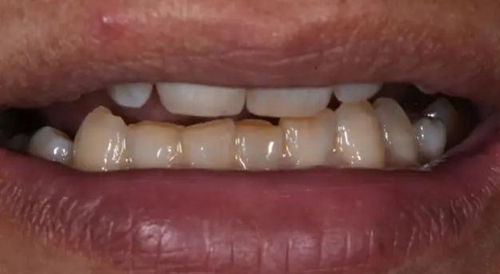

修復(fù)體試戴,修復(fù)體和原牙顏色上有輕微差異,不過患者本人非常滿意。

修復(fù)后正面口內(nèi)微笑照。